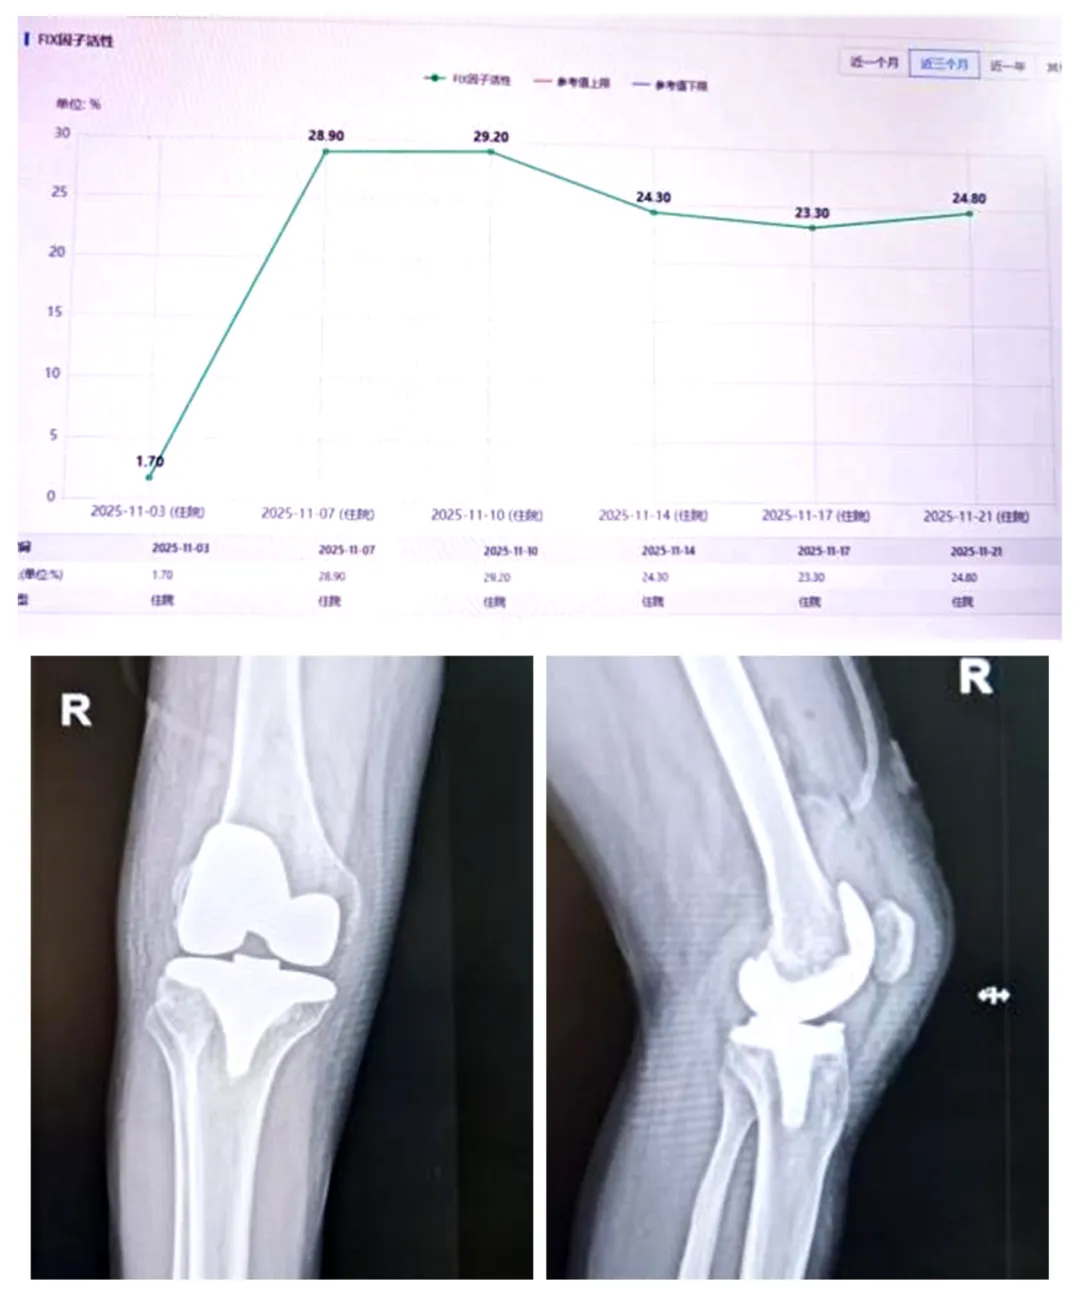

34岁的李先生,因血友病B型长期受膝关节反复出血困扰,疼痛加剧,严重影响生活。经术前凝血因子精准替代治疗、术中精细操作与止血、术后系统康复,患者顺利完成膝关节置换。术后一个月,疼痛显著缓解,关节功能逐步恢复。

65岁的刘先生,同样为血友病B型,因膝关节严重疼痛活动受限,日常依赖轮椅。经全面评估、微创手术与术后抗感染管理,患者成功接受膝关节置换。术后六个月,关节功能明显改善,已可自主上下楼梯,重返日常生活。